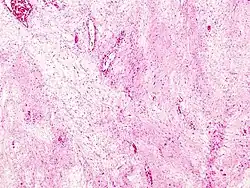

Hiperemia passiva ou congestão possui uma coloração azul-avermelhada intensificada nas áreas afetadas, de acordo com o acúmulo de sangue venoso. Esta coloração aumenta quando há um aumento da concentração de hemoglobina não-oxigenada no sangue. Decorre da redução da drenagem venosa, que provoca distensão das veias distais, vênulas e capilares; por isso mesmo, a região comprometida adquire coloração vermelho-escura devido à alta concentração de hemoglobina desoxigenada. Pode ser localizada (obstrução de uma veia) ou sistêmica (insuficiência cardíaca)[1]. Congestão pode ser causada por obstrução extrínseca ou intrínseca de uma veia (compressão do vaso, trombose, torsão de pedículo vascular etc.) ou por redução do retorno venoso, como acontece na insuficiência cardíaca. Na insuficiência cardíaca esquerda ou casos de estenose ou insuficiência mitral, surge congestão pulmonar; na insuficiência cardíaca direita, há congestão sistêmica. Na congestão aguda, os vasos estão distendidos e o órgão é mais pesado; na crônica, o órgão pode sofrer hipotrofia e apresentar micro-hemorragias antigas. As hiperremias passivas mais importantes são as dos pulmões, do fígado e do baço[2].

Congestão pulmonar

Os capilares alveolares encontram-se dilatados e os septos tornam-se alargados pelo edema intersticial; em longo prazo, os septos sofrem fibrose e ficam espessados. Por causa de microrupturas de capilares, há passagem de hemácias para os alvéolos e sua fagocitose pelos macrófagos alveolares, os quais passam a constituir as chamadas "células da insuficiência cardíaca".